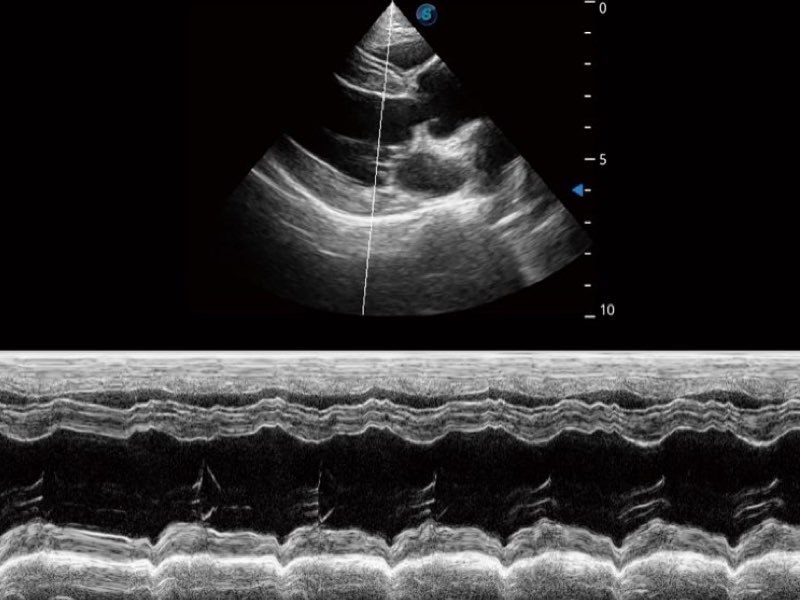

Przy pracach nad aparatem ProPet 60 uwzględniono najważniejsze preferencje i potrzeby weterynarzy, oferując finalnie przystępne cenowo i odpowiednio wyważone połączenie znakomitej precyzji klinicznej, zwiększonej wydajności i przemyślanego przebiegu pracy, niezastąpione w codziennej praktyce weterynaryjnej. Dzięki dostępowi do pełnej gamy głowic HD rozwiązanie to spełnia wszystkie potrzeby w zakresie obrazowania, umożliwiając wykonywanie badań jamy brzusznej, małych narządów, ortopedycznych, badań podczas rozrodu, a nawet badań serca i klatki piersiowej, a to wszystko przy doskonałym stosunku jakości do ceny.